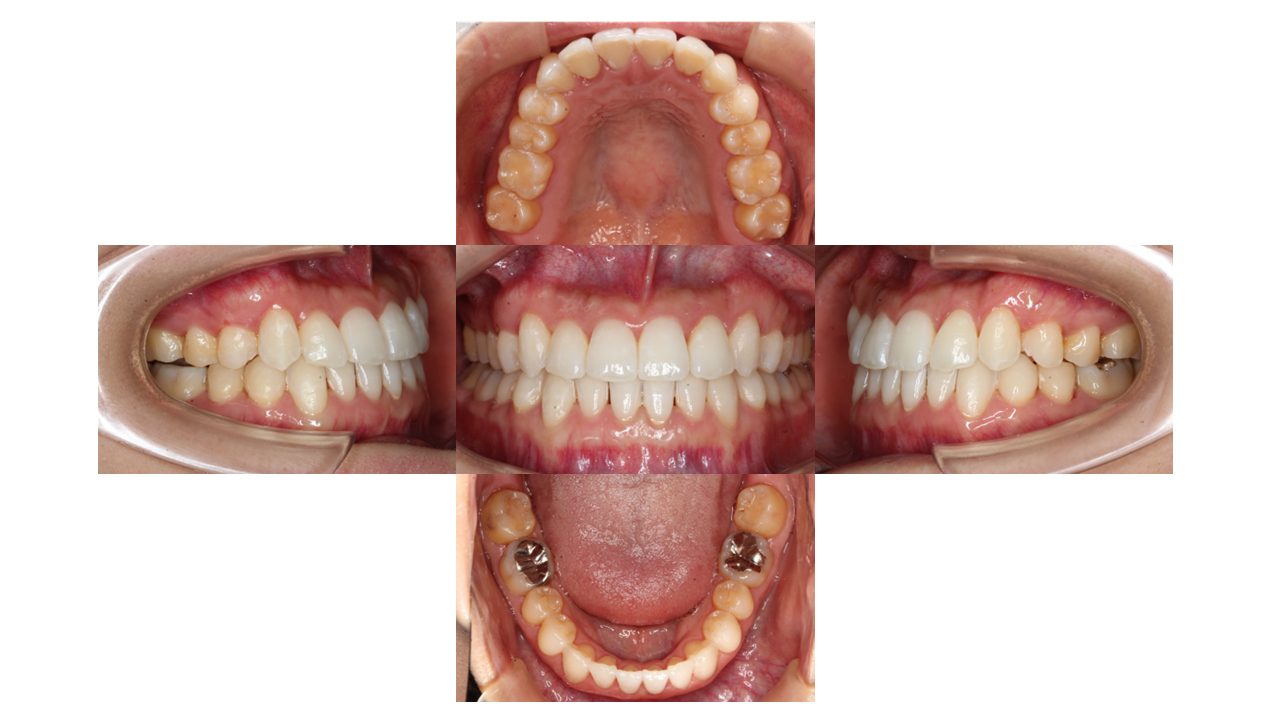

3年6ヶ月経過の口腔内の状態です。

上下の凸凹・噛み合わせが改善したとご満足いただきました。